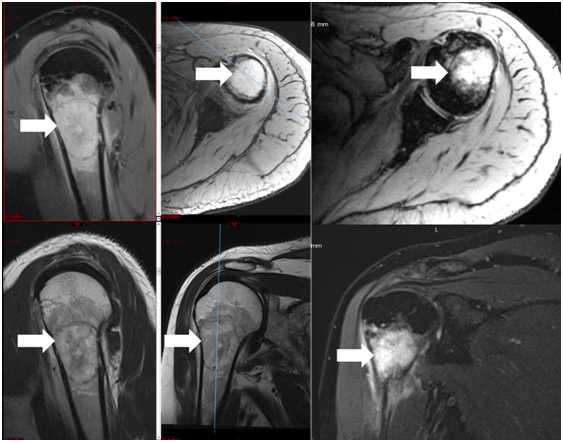

Figure 3 Magnetic resonance with a solid mass observed in the left lung.

Figure 4 Magnetic resonance shows a left humeral lesion of neoplastic appearance.

The patient consulted with a cardiology team where an electrocardiogram and an exercise test were performed, being reported normal. He was then referred to the orthopedics service due to shoulder pain persistence. A shoulder x-ray showed a tumor in the left thorax measuring 78.99mm in diameter (Figure 1). In follow up studies, a left humeral lesion of neoplastic appearance was revealed. In the magnetic resonance an intramedullary lesion is reported in the sternum, incidentally, a solid mass is observed in the left lung, it also shows tendinitis of the rotator cuff and subacromial impingement (Figures 2-4). Therefore, it is decided to perform a Computed Tomography scan which reported atelectasis mainly in the left upper lobe and a tumor measuring 65mm (Figure 5). The Positron Emission Tomography - Computed Tomography scan result was an increase of the metabolism by neoplastic activity, lymphadenopathy and bone lesions, hepatosplenomegaly and non- specific alterations in the colon (Figure 6).